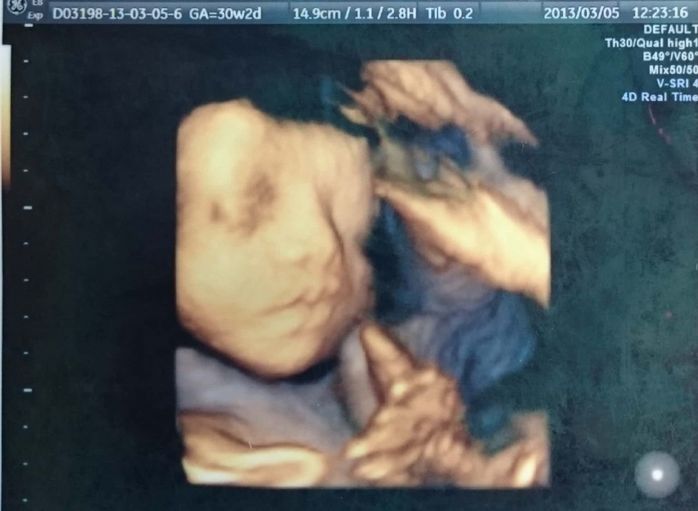

<妊娠後期> 妊娠30週~34週。夫に似ていることが判明!

妊娠30週のエコー写真 再びの3D写真。今見ると、すでに面影あり

14.9cm(3Dのエコー写真では何を測ったかの情報記載がないため、「9.6cm」という数字が何を表しているのかは不明。)

見たいと言ったら見せてくれた3Dエコー。表情がしっかりと分かります。その当時は、「赤ちゃんの人形みたいに見えて、そんなに特徴が分からないな」と思いましたが、今見てみると、息子の寝顔そのまま。面影がかなりあります。私のおなかも大きくなり、歩くペースも遅くなっていた頃でしたが、先生に確認をして隣県へ2泊3日のマタニティ旅行をしました。